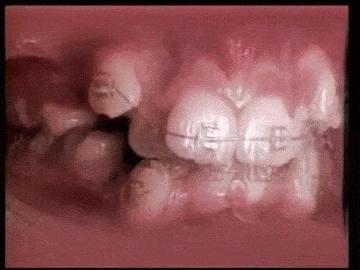

牙齿矫正,其原理就是牙槽骨改建的过程,利用的就是牙齿移动、牙槽骨跟随生长的机制。

我们给牙齿施加一个外力,牙齿就会在牙槽骨里缓慢的移动,而受到挤压的牙槽骨会不停的向牙齿移动方向生长,以保持牙齿周围牙槽骨的厚度,而移动反方向的牙槽骨就会慢慢被吸收,回归到正常的厚度!

简单来说就是:牙齿受力→传递给牙槽骨→牙槽骨生长→牙齿移动。